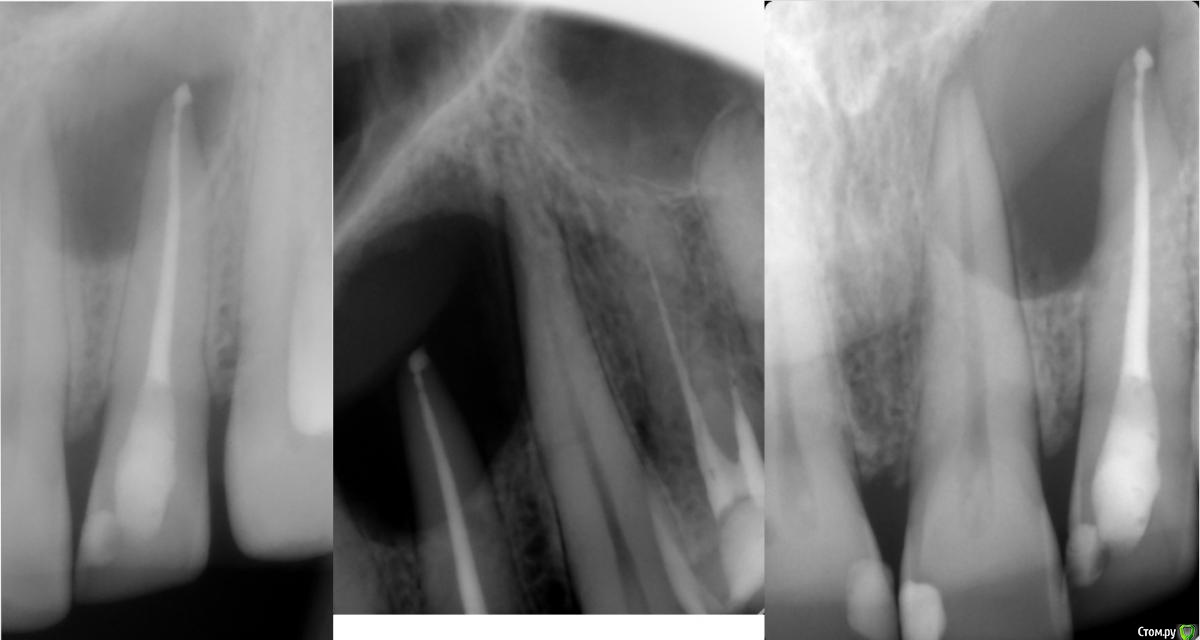

Fred Опубликовано 2 марта, 2017 Поделиться Опубликовано 2 марта, 2017 Я до сих пор толком не разбираюсь в "кистологии". Давайте и на этом форуме побеседуем. Теоретический вопрос - исчезнет ли киста в 100% случаев, если СКК стерилизировать и стерильность ее поддерживать на продолжительном отрезке времени? "Давайте обновим знания в "кистологии".Обратилась ко мне пациента по почте с кистоподобным образованием в области верхней челюсти, у передних зубов (прилагаю ее снимки в первой картинке: первый снимок - полгода назад, другие - на днях). Недавняя моя неудача с много раз презентированным на форумах случаях с кистообразным поражением заставило меня посидеть с литературой и еще раз понять, что же такое происходит во время таких поражений, и что мешает возникнуть заживлению Пациентка утверждала, что канал ей пломбировали года 3 назад, но теперь снова возникла симптоматика и опухание. Рядомстоящие витальные, но резец уже депульпировали, так как собираются кисту вырезать.Я еще раз хочу разобраться, если киста стерильна, то почему возникает симптоматика? Может симптоматику в таких случаях поддерживает то, что мы не можем идеально запломбировать канал, и несмотря на красивую рнг-картинку, мы имеем некачественную обтурацию в апексе, которая и поддерживает временно обостряющуюся клинику? Может образованию не дает возможность исчезнуть то, что это пузырь с жидкостью, хоть и стерильный, и в нем не могут возникнуть репарационные процессы, так как в нем нет кровотока? Может нужно все-таки его насильно сдувать, сплющивать, вырезать? Вчера прочитал раздел Кастеллучи про периапикальные поражения (обновил знания, давно за стоматологическими книгами не сидел), и понял, что все это лечится либо банальной эндодонтией, либо ретроградкой, если эндо не получилось. Никаких специальных хирургических методов, никаких вырезаний, никаких жертв витальности соседних зубов.Так нужен ли специальный подход к "кистам"?Побеседуем?Кто захочет тоже почитать Кастеллучи, но не имеет, просите, дам ссылку или перешлю." 3 Ссылка на комментарий

Fred Опубликовано 2 марта, 2017 Автор Поделиться Опубликовано 2 марта, 2017 Тут снимки пациентки получились на третьей картинке, той, что без комментариев. Ссылка на комментарий